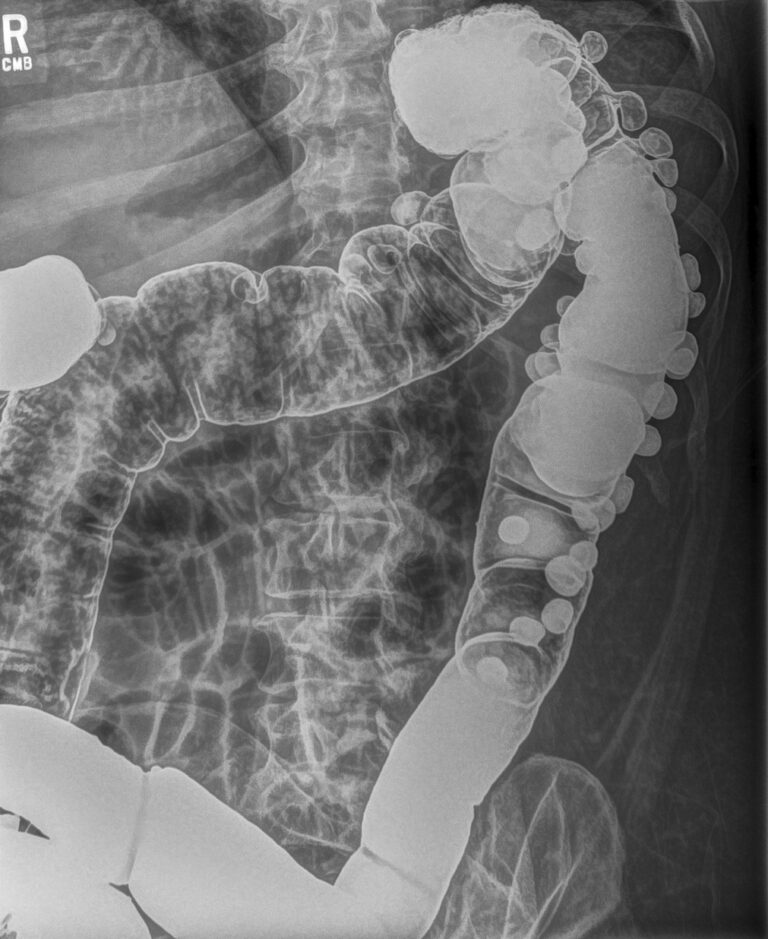

MUSICA3+ abdomen+

Abdominale røntgenoptagelser af store patienter er scatter-dominerede og giver ofte mudrede billeder, hvor organgrænser og katetre er svære at skelne. Abdomen+ forbedrer visualiseringen uden at overforstærke irrelevante detaljer.

- Skarpere afgrænsning af tarmvæg, nyre, lever og blære

- Bedre fremstilling af katetre, stenter, suturer og stomi